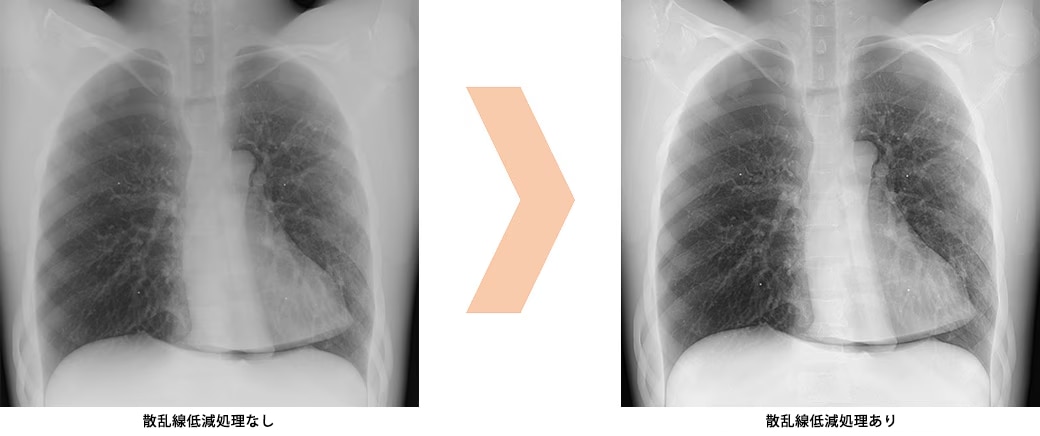

散乱線低減処理で業務の負担を軽減 OPTION

散乱線によるコントラスト低減を抑制することでグリッドを使わずに撮影が行えます。病棟など正確なアライメントが難しい状況で有用です。またグリッド持ち運びや着脱の手間がなくなります。